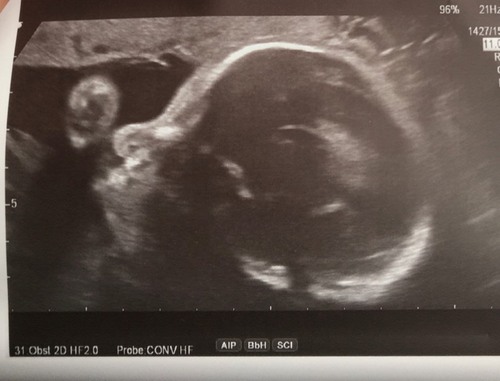

Echo’s kunnen een enorm verkeerd beeld geven. Je baby wordt echt niet met een haviksneus geboren.

Ik heb echt nog nooit een baby met een haviksneus gezien! Snap wel wat je bedoelt maar denk dat t schaduw is ofzo. Maar echt elk babytje heeft een klein schattig knopje als neus, zul je wel zien hihi.

Neeeee joh gekkie. Door geluidgolven lijkt je baby soms ook op een alien.

Dit kan misschien ook zijn doordat het neusje wordt platgeduwd in de baarmoeder als ze tegen de kant zit. Hoe dan ook, echo's geven altijd een heel vertekend beeld 😄

Het is een doorsnede, geen silhouet :) Dus misschien net op een ongunstig moment vastgelegd. Platgedrukt tegen de wand kan ook nog. Geen zorgen om maken hoor, echo's vertekenen.

Het lijkt alsof ze gewoon tegen de wand aanligt en hierdoor haar neusje word plat gedrukt! Denk dat het wel losloopt ☺️

Maak je geen zorgen. Je baby krijgt steeds minder plek en de kans is groot dat het juist met de geluidsgolven en tegen de baarmoederwand aanliggen net even mis gegaan is. Ik heb nog nooit kromme neusjes gezien bij baby’s die pasgeboren waren. Komt allemaal goed.

Dit is een vertekend beeld, zo komt het er in het echt niet uit te zien 😉